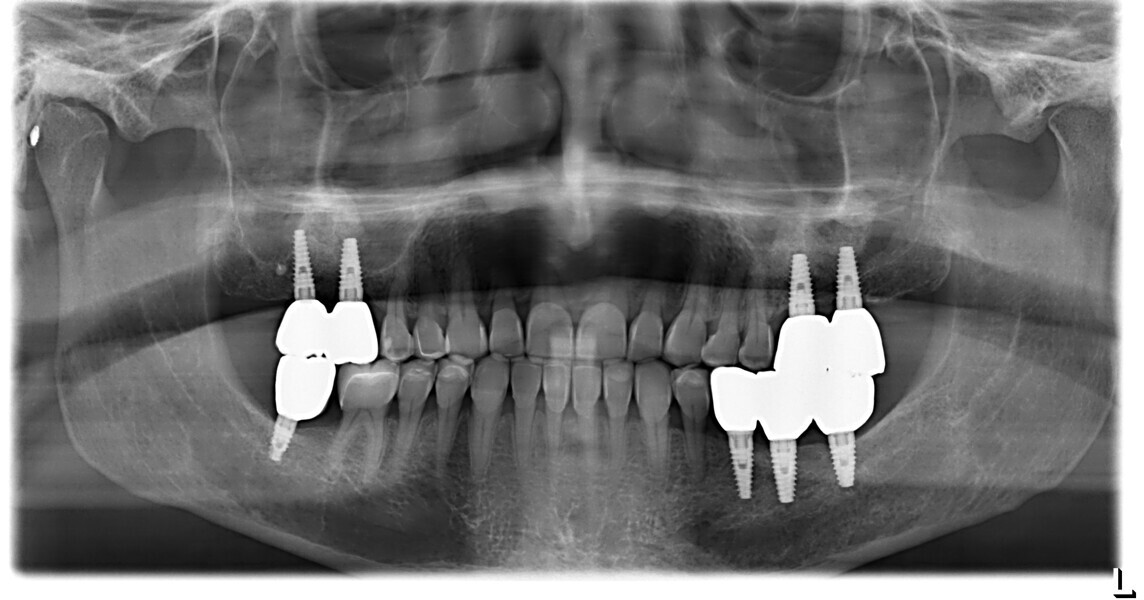

The 58-year-old patient wished to improve his oral aesthetics and function, complaining of mobility of the posterior teeth and wear of the anterior teeth. After data collection, a very complex situation was identified (Figs. 11–13):

1. severe periodontitis with poor prognosis of some teeth;

2. anterior crossbite;

3. severe wear mainly of the anterior teeth and compensatory eruption;38

3. aetiological periodontal therapy and extraction of the teeth with a poor prognosis;

4. realignment of the teeth with aligners;

5. sinus lift for bone regeneration and implant placement with periodontal surgery where needed; and

6. ceramic veneers in the anterior area and crowns on the implants in the posterior area.

This patient, like all patients requiring interdisciplinary rehabilitation, had to first undergo periodontal treatment and caries restoration (Fig. 17). At the same time, it was important to rehabilitate swallowing with Froggymouth and relax the masticatory muscles and relieve the TMJs with an occlusal device. We could then study the orthodontic treatment plan using Invisalign ClinCheck (Align Technology) and showed the treatment plan to the interdisciplinary team and to the patient (Fig. 18). We were then able to create the correct sequence of orthodontic treatment, bone augmentation and implant surgery needed for the posterior edentulous spaces.

After the first phase of aligner treatment, we had achieved better inter-arch coherence, better maxillary arch expansion, and some space for improving the anterior tooth proportions restoratively (Fig. 19). We then temporarily restored the anterior teeth directly with composite, closing the spaces, improving the tooth proportions and further increasing the maxillary arch expansion (Fig. 20). We used restorative arch expansion to reduce the orthodontic destabilisation of the teeth to achieve the correct inter-arch coherence and retain the teeth in the cortical bone.38 A refinement aligner phase was undertaken to improve the final alignment of the gingival zenith and to improve the inter-arch coherence (Fig. 21). The periods of the first orthodontic phase and of the refinement were used to augment the mandibular and maxillary bone and to place the implants (Fig. 22). At the end of the orthodontic treatment, the case was finalised with ceramic veneers in the anterior area and temporary restorations on the implants in the posterior area (Figs. 23–26).

To monitor patient progress and the biological situation over time, we conducted periodic examination using radiographs and clinical assessment. Additionally, we evaluated the functional behaviour of the tongue and mastication using the swallowing analysis mentioned earlier and the G-test (chewing gum mastication test; Fig. 32).26